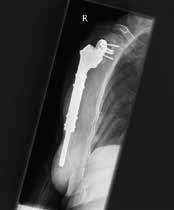

Weltweit werden die meisten Schulterprothesen von Operateuren implantiert, die weniger als zehn Implantationen pro Jahr durchführen 1. Das bringt die Gefahr mit sich, dass sich die Zahl der Komplikationen erhöht. Die inverse Schulterprothetik führt durchaus zu einer guten Rekonstruktion der Funktion bei Patienten mit Rotatorenmanschettendefekten 2. Durch die Umkehrung von Konvexität am Glenoid und Konkavität am Humerus wird das Drehzentrum distalisiert und medialisiert, was zu einer Reduktion des Drehmoments und zu einem zusätzlichen Recruitment von Deltafasern führt (Abb. 1a u. b) 3.

Distalisierung:

- Vorteil: Verbesserung des Momentarms für den M. deltoideus um 25 %

Medialisierung:

- Vorteil: Rotationszentrum in Projektion auf den glenoidalen Knochen reduziert die Implantat-Knochen-Belastung

- Nachteile: Scapula-Notching, Verlust der Deltoidkontur, Reduktion des Momentarms für den M. infraspinatus